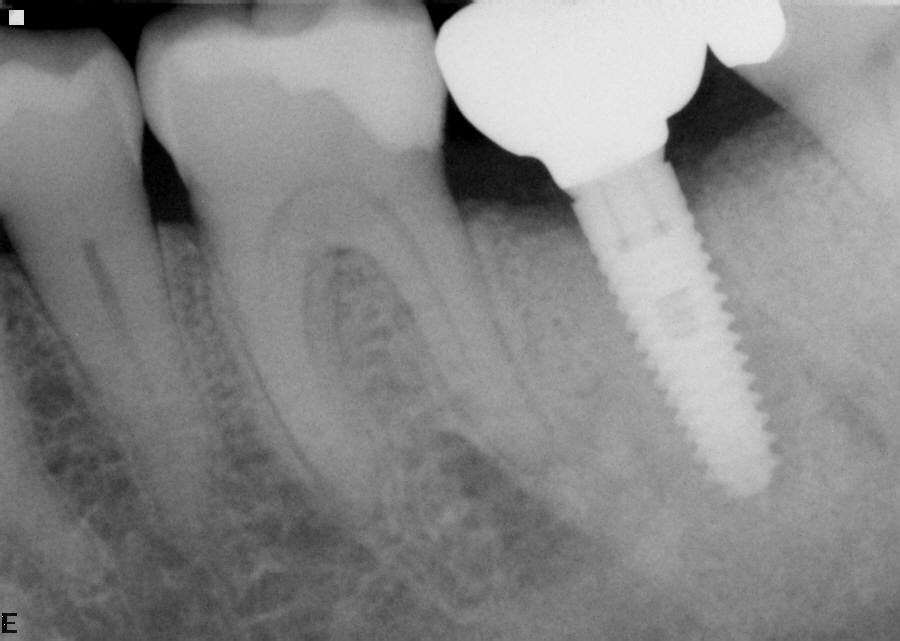

Initial x-ray showing bone loss around implants placed 5 years ago in another dental clinic